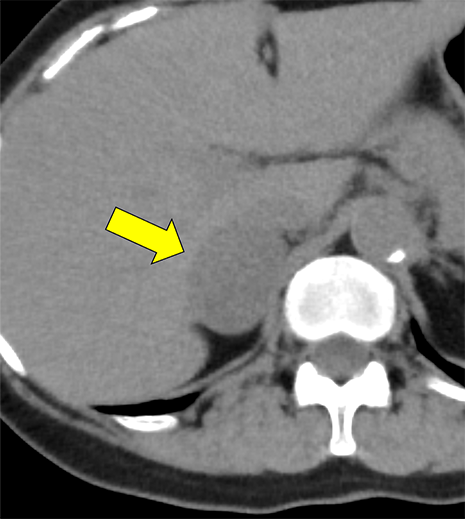

本例は、偶発的に指摘された右副腎腫瘍である。高血圧はあるが内服せず経過観察されている患者で、1cm/5年程度の非常に緩徐な増大を示す多血性の腫瘍を認める。腫瘍はI-123MIBGシンチ陰性であり、内分泌内科での精査においてもホルモン産生を疑う所見に乏しく、褐色細胞腫よりも海綿状血管腫が疑われていた。しかし、増大傾向があり破裂や出血のリスクなども考慮されて手術の方針となった。手術中に血圧の変動を認め、病理で褐色細胞腫の診断となった。

褐色細胞腫は副腎髄質に存在するクロム親和性細胞に由来する腫瘍で、カテコールアミンなど種々の生理活性物質を産生する。ダイナミック造影で動脈相での強い濃染と持続する造影効果が特徴とされ、サイズが大きい病変は嚢胞変性や出血、壊死を伴うことが多い。かつては、臨床的に褐色細胞腫が疑われる場合、ヨード造影剤の投与はカテコールアミンの過剰放出を誘発し、高血圧クリーゼを引き起こす可能性があるため原則禁忌とされていた。しかし、現在汎用されている非イオン性・低浸透圧性造影剤であればこの現象は起こらないとの報告もあり、European Society of Urogenital Radiology Guidelines on Contrast Media, ver 10.0では、「経静脈的ヨード造影剤の投与をする場合でも特別な準備の必要はない」と記載されている。イオプロミドの電子添文上は、禁忌にはなっていないものの、「慎重に投与すること」との記載になっている。本例では、血管腫疑いとして合計5回の造影CTが行われているが、血圧変動や頭痛、動悸などの症状は一度も認められなかった。

本例の画像所見として、褐色細胞腫としてダイナミック造影の濃染パターンは典型的ともいえたが、大きさの割に変性が乏しい点、MIBGシンチでの核種集積に乏しい点、ホルモン産生に乏しい点など非典型的な要素が複数存在し、海綿状血管腫を除外しきれなかった。なお、褐色細胞腫はRET遺伝子変異による多発性内分泌腺腫症(multiple endocrine neoplasia;MEN)type 2A・2B、VHL遺伝子によるvon Hippel-Lindau病、NF1遺伝子による神経線維腫症1型に生じることが知られているが、これらの疾患を想起させるような他病変は本例には見つかっていない。

腺腫や骨髄脂肪腫など良性と断定できない副腎腫瘍の鑑別をする際、大きい病変であれば褐色細胞腫や副腎癌、悪性リンパ腫などが考慮される。核医学検査も有用ではあるが、本例のように偽陰性となることも稀にあり、その際はダイナミック造影パターン、血管への浸潤、転移の有無などから判断しなければならない。適切なタイミングで撮像されたダイナミック造影CTは、多血性病変であるかの評価、周囲の血管との関係性、多血性の転移巣の有無などの判断に寄与し、診断の重要な手がかりとなると考える。